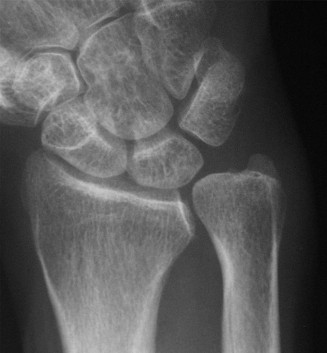

The same patient is seen in clinic 4 weeks later and still has persistent pain. An x-ray ordered at this time reveals the findings shown (Fig. 3–2). What is the more prudent thing to do next?

Figure 3–2(©) Sunil Thirkannad and Christine M. Kleinert.

The correct answer is (A). The x-ray reveals a fracture of the scaphoid. Healing rates are around 75% with nonsurgical treatment in adults compared to around 95% after surgery. However, since the patient is a 14-year-old child and has already been in a splint for 4 weeks, a prudent course would be to continue splinting for a further 2 to 4 weeks.